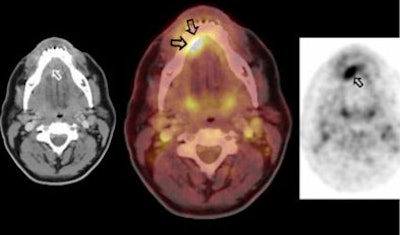

![]() |

| A 48-year-old male with carcinoma at the base of the tongue. CT and PET images (left and right, respectively) show the pathology. However, the fused PET/CT image indicates osseous infiltration, which was later confirmed by histological pathology. Images courtesy of Dr. Patrick Veit, the University Hospital of Essen, and the ECR. |